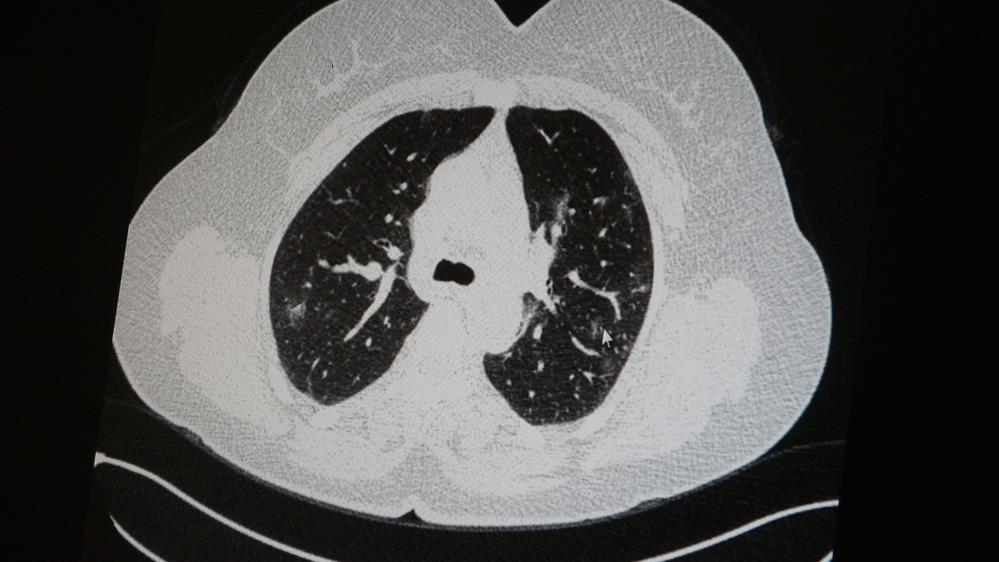

Medical Park Elazığ Hastanesi Göğüs Hastalıkları Uzmanı Dr. Cebrail Azar, geçtiğimiz yıla oranla yoğun bakımda yatan hastaların yaş ortalamasının 65'ten 35'lere kadar düştüğüne dikkat çekti. Genç olduğu halde aşı olmayanlarda hastalığın ağır seyrettiğini ifade eden Uzm. Dr. Azar, "Ben gencim, benim bağışıklık sistemim kuvvetli" diyen genç bir hastanın akciğerlerinde ciddi lekelenmelerin olduğunu ve koronavirüs zatürresi olduğunu gördüklerini belirtti.

AŞI OLMAYAN HASTANIN AKCİĞER TOMOGRAFİSİ: